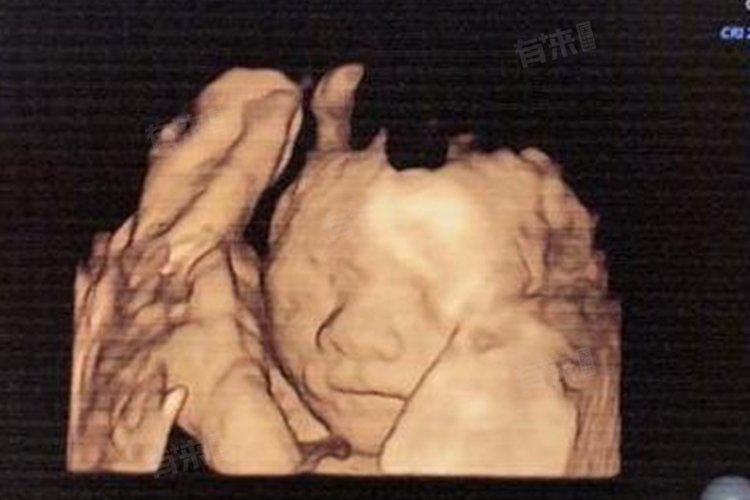

四维彩超是一项重要的孕期检查,可以通过动态、立体的观察胎儿的结构,来判断胎儿是否存在畸形。通常在怀孕22-26周,尤其是24周左右做最好。但请注意,具体检查时间还需根据孕妇和胎儿的具体情况来确定。

- 四维彩超的主要检查内容包括胎儿的头颅、面部、脊柱、四肢以及内脏器官等,可以排除胎儿是否存在面部畸形、神经系统畸形、消化系统畸形、泌尿系统畸形以及其他畸形,因此四维彩超对于保障胎儿的健康具有重要意义。